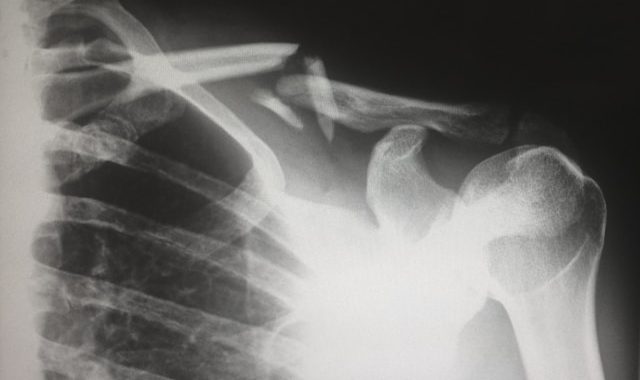

Existen varias modalidades de imagenología, como radiografías, tomografías computarizadas (TC), resonancias magnéticas (RM) y ultrasonidos. Cada técnica tiene sus ventajas específicas dependiendo del tipo de examen necesario. Por ejemplo, las radiografías son especialmente útiles para examinar huesos y detectar fracturas.

- Imágenes precisas y detalladas de huesos, tejidos blandos y órganos, mejorando la precisión diagnóstica y la planificación de intervenciones.

- Amplia aplicación clínica, desde el diagnóstico de fracturas y enfermedades respiratorias hasta exámenes dentales y controles rutinarios.